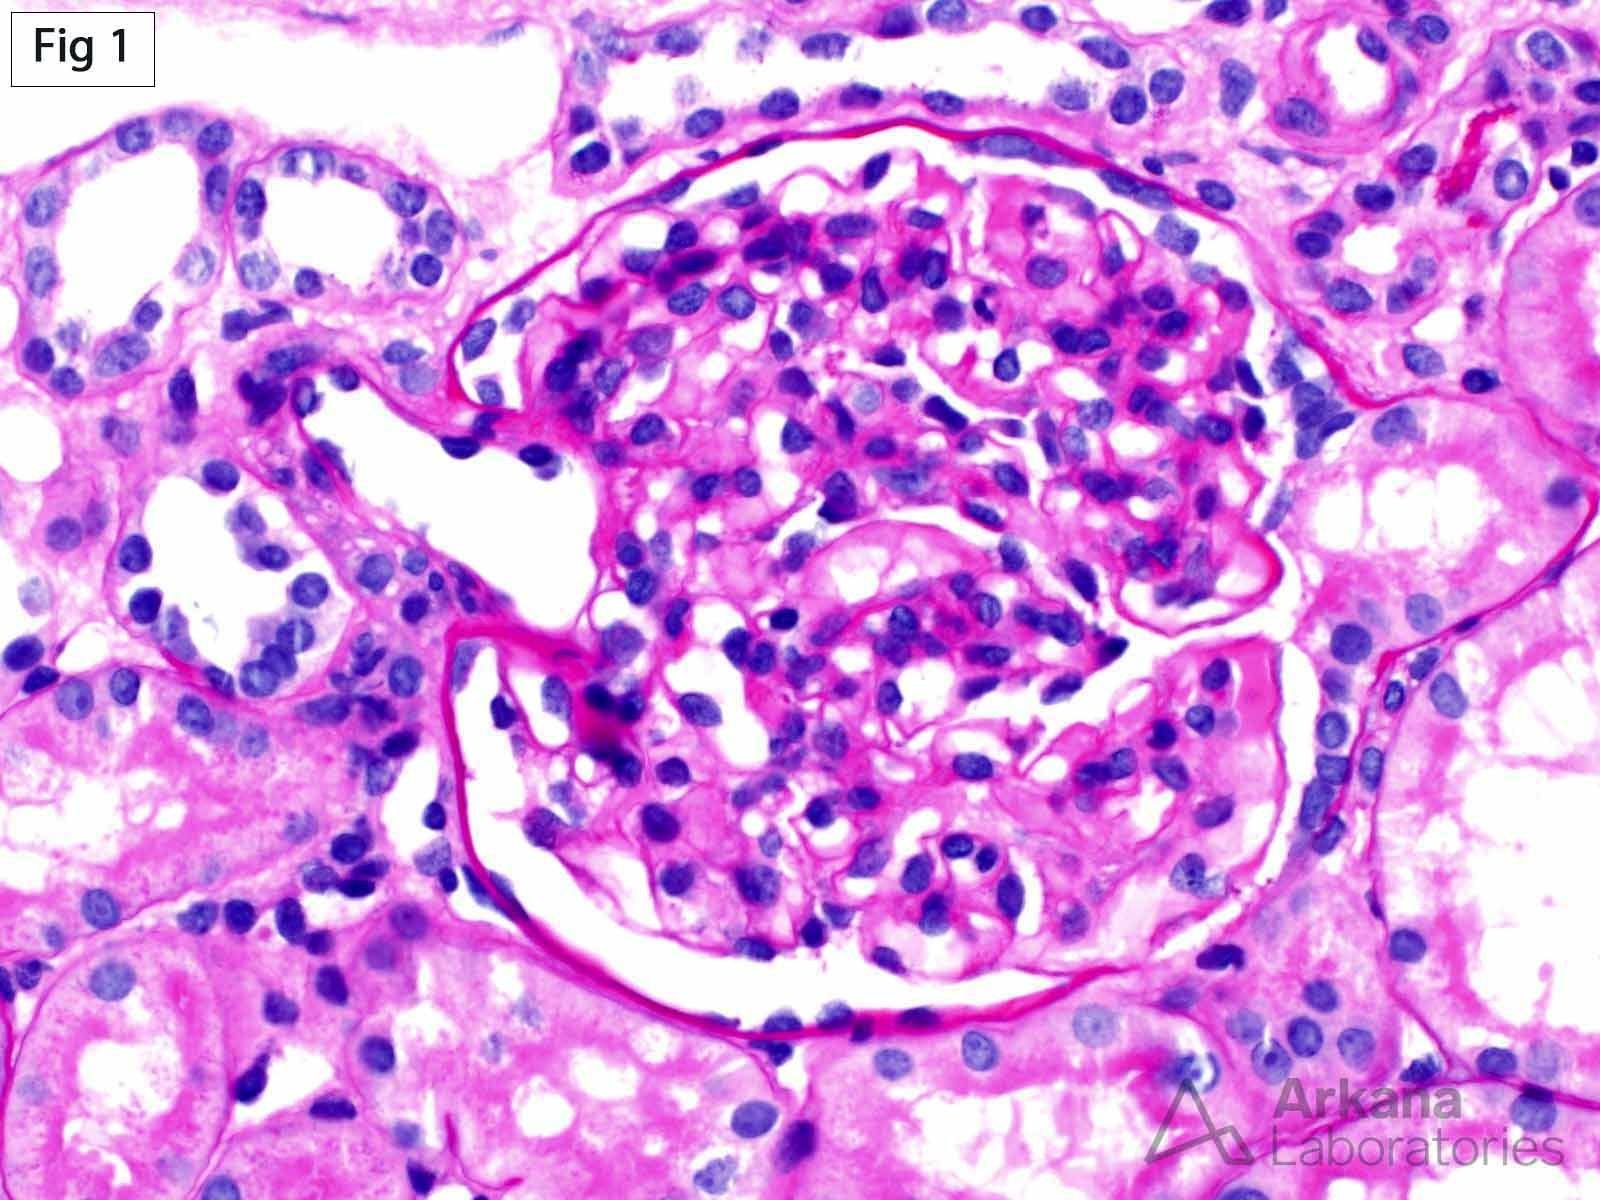

Master Pulse Volume Recording (PVR) with our comprehensive guide. Learn how this essential non-invasive vascular test detects peripheral artery disease by measuring limb blood flow. Understand PVR waveform analysis, arterial testing procedures, and clinical diagnostic applications to improve patient outcomes in vascular medicine. Explore expert insights into interpreting vascular oscillations and identifying circulation issues effectively.